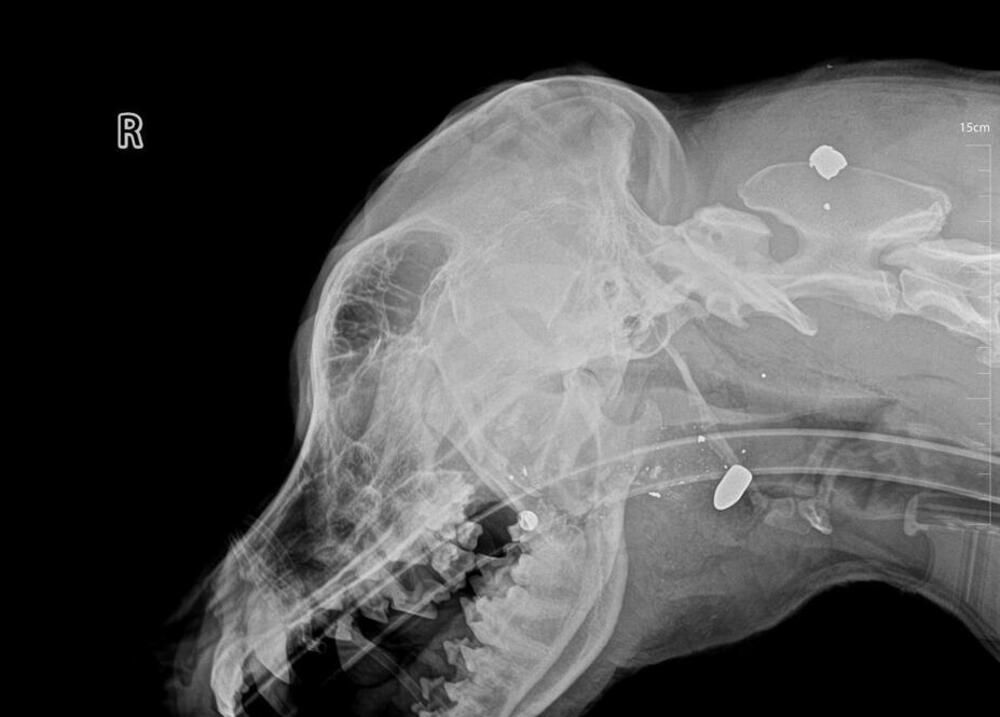

Aktivisti za zaštitu životinja navode da su u psa ispaljena tri metka (rentgenski snimak)

Aktivisti za zaštitu životinja navode da su u psa ispaljena tri metka (rentgenski snimak)foto: Privatna arhiva

“Zbog straha tih građana pozvana je komunalna policija, a potom i redovna policija, s obzirom na to da Cetinje, i pored zakonske obaveze još od 2010. godine, nema nadležnu (za to opremljenu i obučenu) službu za hvatanje životinja, niti azil za pse. Usljed neznanja i neobučenosti policijskih službenika, došlo je do nezapamćenog i monstruoznog čina: policajac je psa, dok je bio vezan za drvo povocem, isprskao biber sprejom, a zatim ga upucao sa tri metka u grkljan i jednim u nogu”, navode i dodaju da je time počinjeno krivično djelo, prekršen Zakon o zaštiti dobrobiti životinja, a događaj “dokaz “potpune nespremnosti državnih institucija da primijene zakon”.